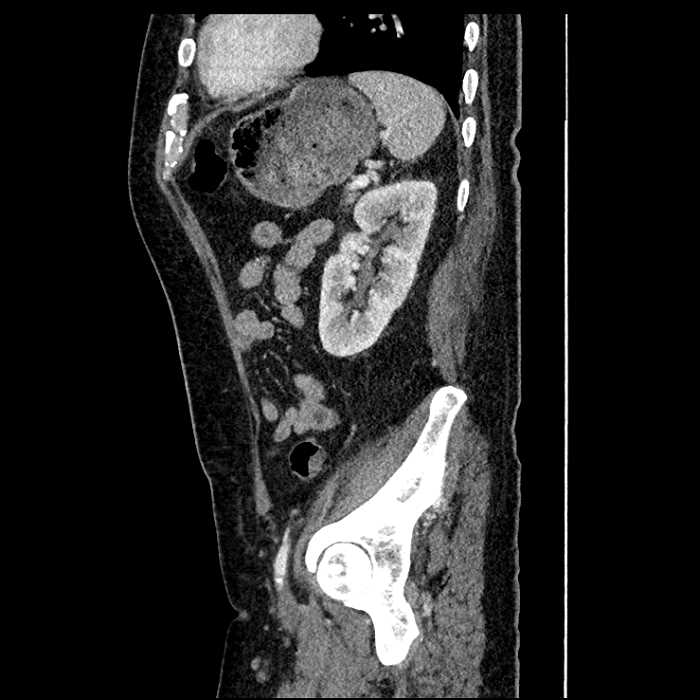

Age: 63

Sex: Male

Indication: Abdominal pain

• Large fluid density structure in hepatic segments 7 and 8 measuring 10 x 7 x 7 cm with internal septation and circumferential ill-defined low density compatible with edema

• Peripherally enhancing subcapsular collections along the anterior margin of the left hepatic lobe measuring 3 x 1 cm and 2 x 1 cm

• Clearly marginated fluid density structure in segment 7 and several other scattered tiny hypodensities, which likely represent cysts

• Mild mural thickening of a segment of the sigmoid colon with adjacent fat stranding and a 1.5 cm fluid and gas collection along the tip of an inflamed diverticulum

• Loss of the normal fat plane between this collection and adjacent loops of small bowel, which demonstrate mural thickening

• Hepatic abscess

Acute sigmoid diverticulitis complicated by a small contained perforation and a large abscess in the right hepatic lobe. Additional small subcapsular abscesses along the anterior margin of the left hepatic lobe.

Additionally, loss of the normal fat plane between the peridiverticular collection and adjacent thickened loops of small bowel raises the potential for an enterocolonic fistula.

Hepatic abscess showing the double target sign with low density internally surrounded by a thin inner enhancing rim (red arrow) and ill-defined outer low density rim (yellow arrow). Blue arrow indicates an internal septation. Red arrows: additional smaller subcapsular abscesses. Red arrow: focal contained perforation associated with diverticulitis.